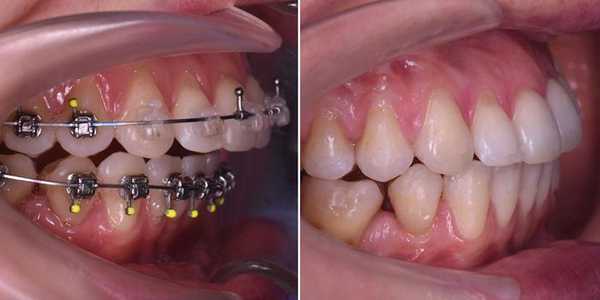

- Установка брекетов, чтобы выровнять зубы перед операцией. Согласовав лечение с хирургом, врач-ортодонт устанавливает брекеты пациенту, чтобы сформировать правильные зубные ряды для успешного хода операции. Срок предоперационного ортодонтического лечения определяется ортодонтом, в среднем составляет от полугода до года.

- Операция. Характер хирургического вмешательства зависит от клинической ситуации, однако все они проводятся с установленной брекет-системой.

- Реабилитация. В ходе реабилитации брекет-система выполняет функцию шинирования - для фиксации и правильного заживления костей челюсти.

- Детализация ортодонтического лечения. После реабилитации врач-ортодонт смыкает зубы пациента в правильное положение, детализирует положение зубов для формирования красивой улыбки.

- Снятие. Когда достигнуто правильное положение и смыкание зубов, ортодонт снимает брекеты и устанавливает ретейнеры. Мы также рекомендуем профессиональную гигиену полости рта, чтобы полностью снять остатки фиксирующего материала и тщательно заполировать зубы после брекетов.

Пример фото дистального прикуса до и после лечения